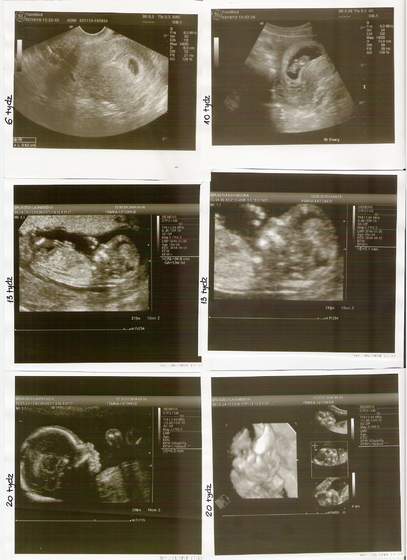

To ja dzisiaj hurtem :-D Zdjęcia córuni (na 99,99%) od 6-20 tygodnia.

Wczoraj byłam na USG połówkowym. Wszystko zmierzone, sprawdzone i policzone.

Mała uciekała co chwilę z przed obiektywu. OStatnie zdjęcie w 3D, ale czarno białe jest mało wyraźne.